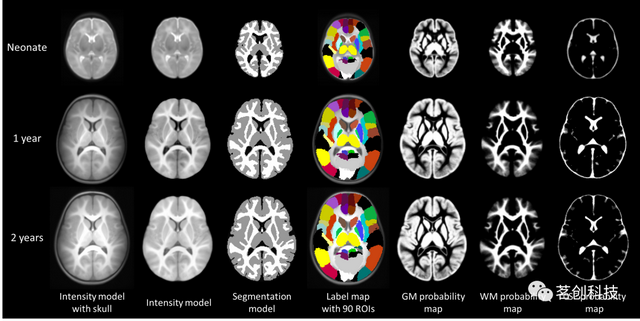

UNC婴儿0-1-2图谱

这是一套针对新生儿、一岁和两岁婴幼儿的纵向时空图谱,共95名。这些新生儿在出生后五周内进行了首次扫描,并在一岁和两岁时进行了纵向扫描。这种纵向设计是避免选择偏差的一个重要特征,这在横截面设计中是不可避免的。该图谱由组平均T1和T2加权图像组成,其中包括灰质、白质和脑脊液的组织概率图,这些图像是使用应用于每张图像的自动图像分割方法创建的。该图集还包含从自动解剖标记(AAL)传播的分割图谱。

下载地址:

https://www.med.unc.edu/bric/ideagroup/software/unc-infant-0-1-2-atlases

或

https://www.nitrc.org/projects/pediatricatlas

来源:Infant brain atlases from neonates to 1- and 2-year-olds.